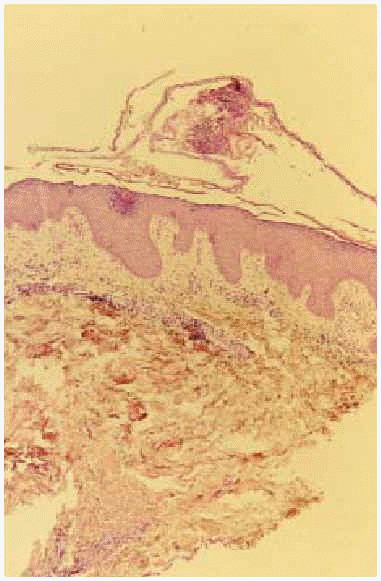

Se realizó una biopsia cutánea, que mostró pústulas subcórneas epidérmicas, junto con un infiltrado perivascular linfocitario en dermis superficial y la presencia de una foliculitis profunda (fig. 6). En la inmunofluorescencia directa se apreciaba un depósito de IgA intercelular a nivel subcórneo (fig. 7). La inmunofluorescencia indirecta fue negativa. En las determinaciones analíticas de sangre y orina realizadas no existía alteración de ningún parámetro, incluyendo los valores de IgA. Se inició tratamiento con dapsona (100 mg/día) con mejora de las lesiones.

Fig 7.--Depósito de IgA entre los queratinocitos.